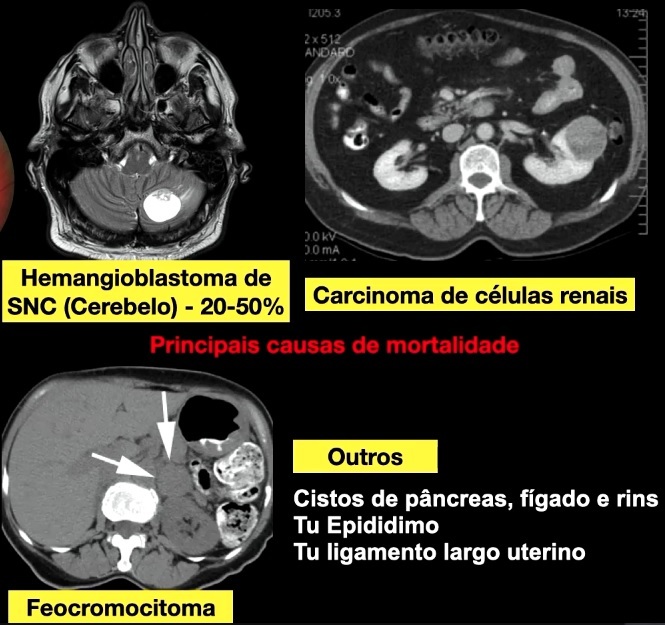

Quais são as principais alterações sistêmicas da Doença de Von-Hipple-Lindau? (4)

Até que idade realizar rastreio sistêmico na VHL? Quem realizará? Quais exames? (4)